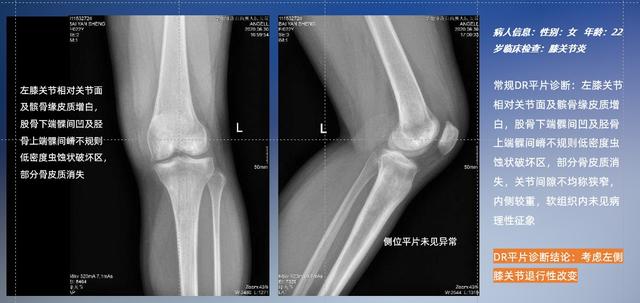

普通平片扫描与WR-3D扫描前后诊断结果对比

以膝关节疾病检查为例,膝关节在解剖学意义上是一种较为复杂的最大关节,由胫骨上端、股骨下端及髌骨组成。在股骨与胫骨的关节面之间存在两块半月板,分别处于内侧、外侧。膝关节的运动主要为伸、屈,在半屈位时可进行小幅度的旋外、旋内运动。随着现代人们体育生活以及肥胖的增加,膝关节疾病出现高发趋势,特别是关节磨损、膝关节炎与骨关节炎等关节退行性改变,长时间的内翻负荷会造成内侧关节软骨、骨性关节面的磨损。目前针对此类疾病的检查主要为平片下的负重位检查、CT检查以及MRI检查,相较于非负重位检查,负重位检查能更加真实反映膝关节结构中胫骨、股骨、髌骨实际对位关系和关节面的形态特征及关节间隙大小,对膝关节骨关节病诊断准确率高。

与此同时,数字化X线摄影技术相较于CTMRI来说,能快速获取真实、直观、满足临床需要的影像。DR的图像具有图像层次丰富、空间分辨力高、影像边缘锐利清晰、密度分辨力高级细微结构表现出色等特点,针对膝关节解剖结构数字化X线摄影技术应用价值很高,尤其是是对骨小梁与骨皮质的显示非常清楚。在负重位状态下,数字化X线三维摄影扫描与重建,能够更好的呈现受检者关节受力改变的状态。德赢VWIN科技创新的WR-3D动态三维数字化X线摄影技术,通过数字化X线摄影完成三维扫描并重建三维影像信息,包括MPR多平面重建、MIP重建以及VR绘制。扫描时间短,剂量相较于CT设备大幅缩减,同时成本更低,在临床诊断以及医疗方案制定中具有极大的价值意义。相较于普通平片下的负重位扫描,负重位动态三维扫描摄影技术能够避免二维状态下的组织结构重叠、密度分辨率不足、组织解剖结构难以分辨等问题,WR-3D支持多角度的动态三维摄影观察,能全面的呈现被检查部位在多个角度下三维影像信息,极大的减少了二维负重位检查的漏诊率。